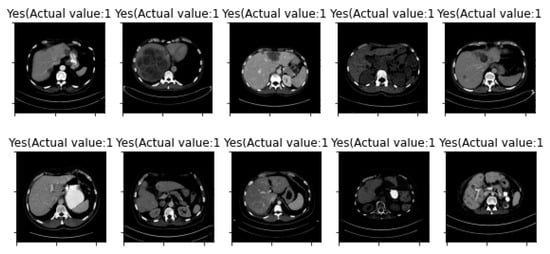

| Image Number | Overlaid Image | Deep Lesion Label | CNN Result | Clinical Radiologist’s Diagnosis | Grad-CAM Helpfulness |

|---|---|---|---|---|---|

| 1 | ![]() | Has Tumor | Has Tumor | Has Tumor | Some |

| 2 | ![]() | Has Tumor | Has Tumor | Has Tumor | Yes |

| 3 | ![]() | Has Tumor | Has Tumor | Has Tumor | Yes |

| 4 | ![]() | Has Tumor | Has Tumor | Has Tumor | Yes |

| 5 | ![]() | Has Tumor | Has Tumor | Has Tumor | Yes |

| 6 | ![]() | No Tumor | Has Tumor | Has Tumor | Yes |

| 7 | ![]() | Has Tumor | Has Tumor | Has Tumor | Yes |

| 8 | ![]() | Has Tumor | Has Tumor | Has Tumor | Yes |

| 9 | ![]() | Has Tumor | Has Tumor | Has Tumor | Some |

| 10 | ![]() | Has Tumor | Has Tumor | Has Tumor | Yes |

| 11 | ![]() | Has Tumor | Has Tumor | No Tumor (Cyst) | Some |

| 12 | ![]() | Has Tumor | Has Tumor | Has Tumor | Yes |

| 13 | ![]() | Has Tumor | Has Tumor | No Tumor | Yes |

| 14 | ![]() | Has Tumor | Has Tumor | No Tumor (Inflammation of the Biliary Tract) | Some |

| 15 | ![]() | No Tumor | Has Tumor | No Tumor (Cyst) | Some |

| 16 | ![]() | Has Tumor | Has Tumor | Has Tumor | Yes |